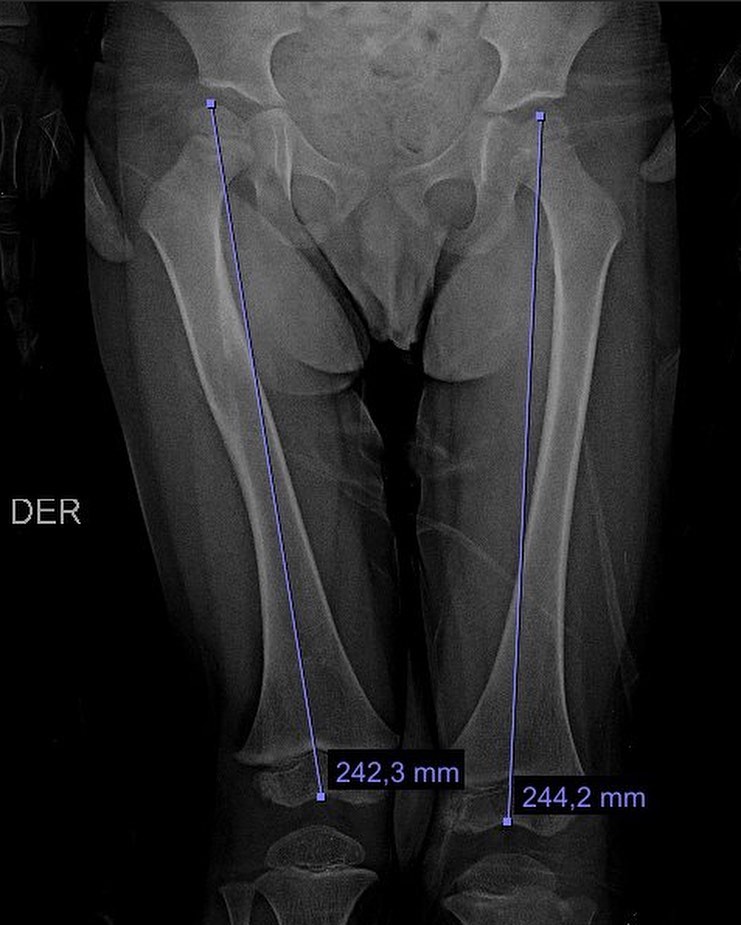

Fractura de fémur

El año pasado mi pacientito Dylan se fracturó el fémur, realizamos tratamiento conservador y ahora está al 💯 Vino a consulta y recibí este delicioso regalo, ¡muchas gracias Dylan!